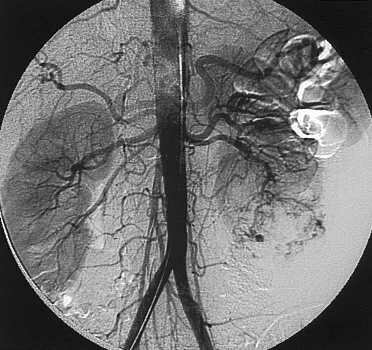

Angiografía Digital

En el 1981 apareció la angiografía digital que ha mejorado el estudio y tratamiento de las patologías vasculares.